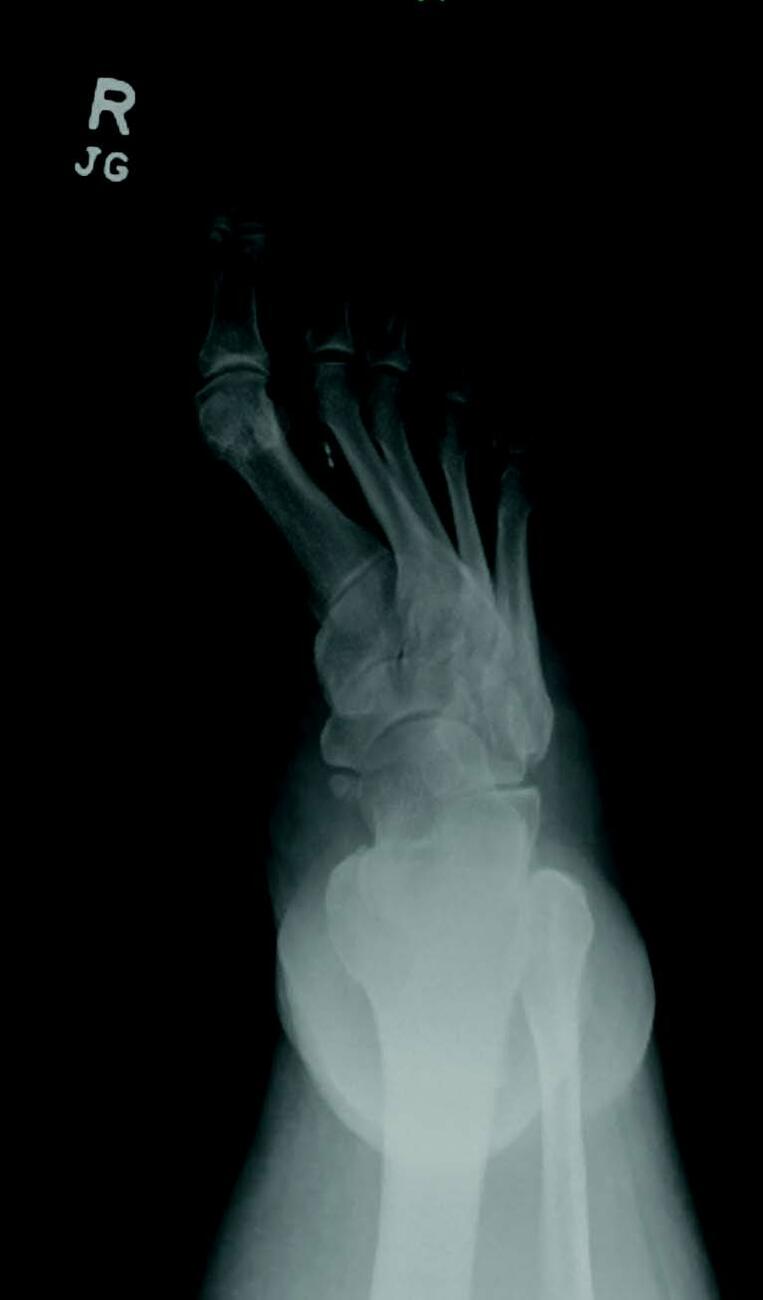

Charcot neuroarthropathy is a tissue-destructive process of the musculoskeletal system in patients with neuropathy.6-9 Most commonly affecting the foot and ankle, Charcot develops from repetitive trauma to an insensate foot. Historically, two theories describe the etiology of Charcot neuroarthropathy: the neurovascular theory; and the neurotraumatic theory. The neurovascular theory proposes that altered autonomics in patients with neuropathy leads to arteriovenous shunting and increased arterial flow, precipitating amplified osteoclastic activity and subsequent bone resorption and fracturing.10-11 The neurotraumatic theory suggests unrecognized trauma in neuropathic patients leads to repetitive injury and subsequent breakdown.12

Regardless of the cause, an acute Charcot foot is a hyperinflammatory event in the setting of immune dysregulation. Jeffcoate and colleagues hypothesized that Charcot foot developed due to the release of pro-inflammatory cytokines in an amplified immunologic response to trauma.12 They proposed a post-traumatic pathway that resulted in increased expression of TNF-α and IL-1ϐ. These cytokines induce increased expression of RANKL, which activates NF-κϐ (a transcription factor), mobilizing osteoclasts for osteolysis. Such a process would be a healthy response to injury, but in the setting of neuropathy, the injured site may sustain repetitive insults. Perhaps these repetitive insults manifest immune dysregulation, leading to an uncontrolled hyperinflammatory state.12-13 There is limited research to support this elegant theory, but there is acceptance of the proposed pathway as the most likely mechanism driving Charcot collapse.

Management of the acute Charcot foot involves management of any present ulceration or infection and aggressive offloading through immobilization to prevent progression of deformity and amplification of the inflammatory cycle.16-17 There is some early evidence to suggest using immunomodulators such as TNF-ɑ inhibitors in the management of acute Charcot foot.18 Bisphosphonates are occasionally part of the treatment for the acute Charcot foot with mixed results.19 Surgical management of the acute Charcot foot is rarely indicated as surgical trauma may worsen the inflammatory cascade, resulting in even more bone resorption.